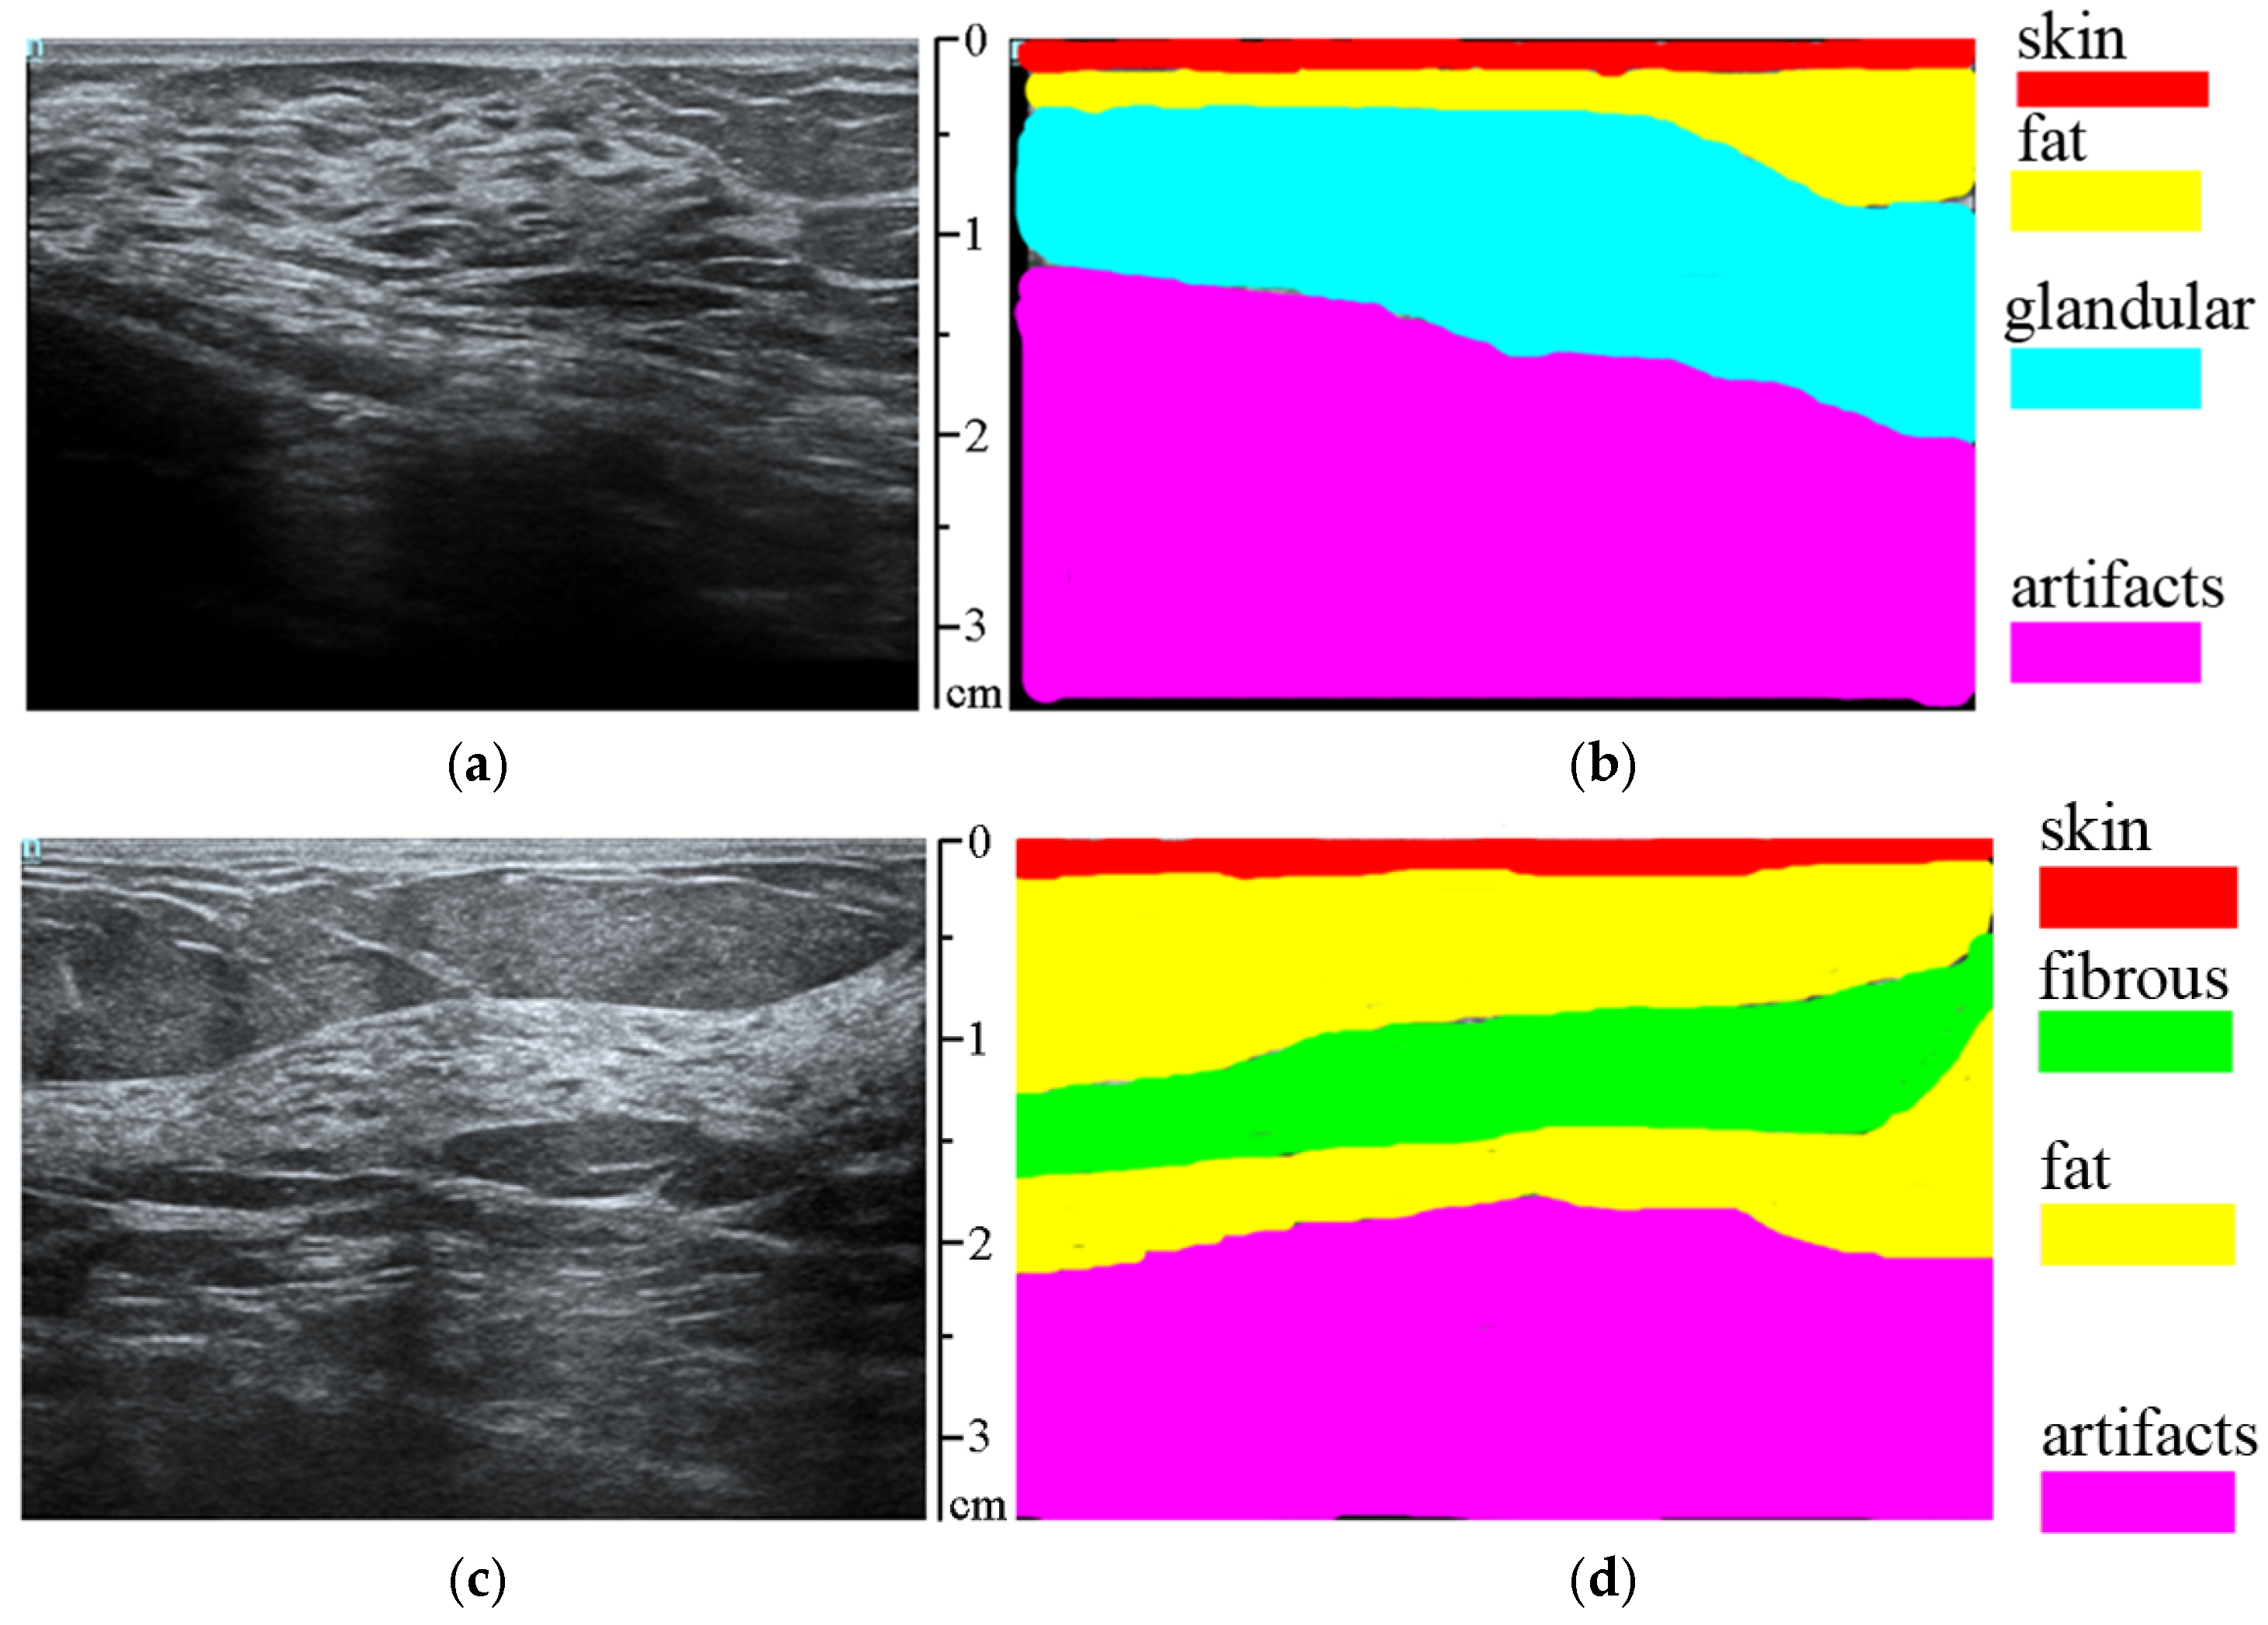

2.2.2. Classification of Normal Tissues

3.1. Classification and Suppression of Normal Tissues